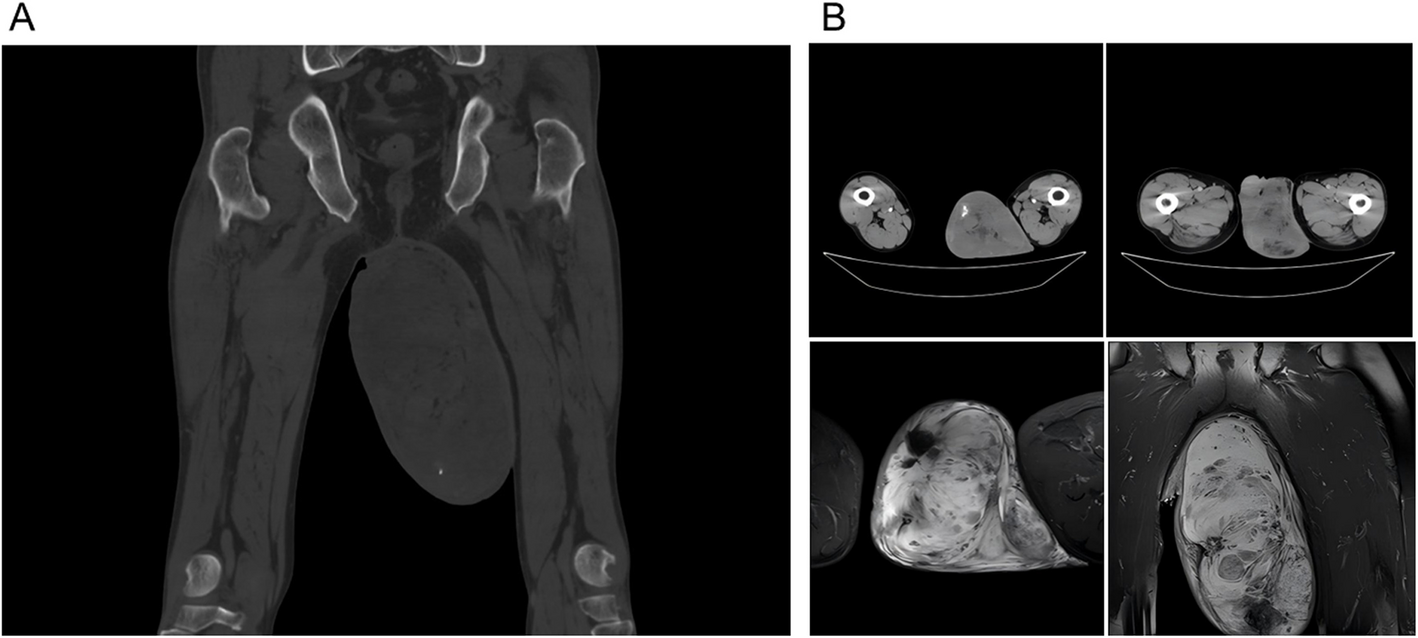

Giant angiomyofibroblastoma of the scrotum: a case report and review of the literature

An angiomyofibroblastoma (AMF) is a rare tumor that primarily occurs in the vulva of women. AMF rarely occurs in the ingui...